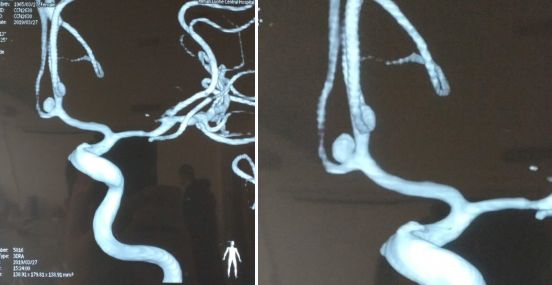

事情发生在3月27日,患者江女士(化名)早上起床后突感头痛,并伴随呕吐,视物成双、言语不清、肢体麻木无力抽搐、意识丧失、大小便失禁等,家人发现后立即送往当地镇医院,行头颅CT提示“蛛网膜下腔出血”,为求进一步治疗,家人急忙将患者转入市中心医院,考虑到颅内动脉瘤的可能,医院按照脑卒中治疗流程对患者进行急诊血管造影,检查结果证实为“前交通动脉动脉瘤破裂”。

▲脑血管造影检查为“前交通动脉瘤破裂”